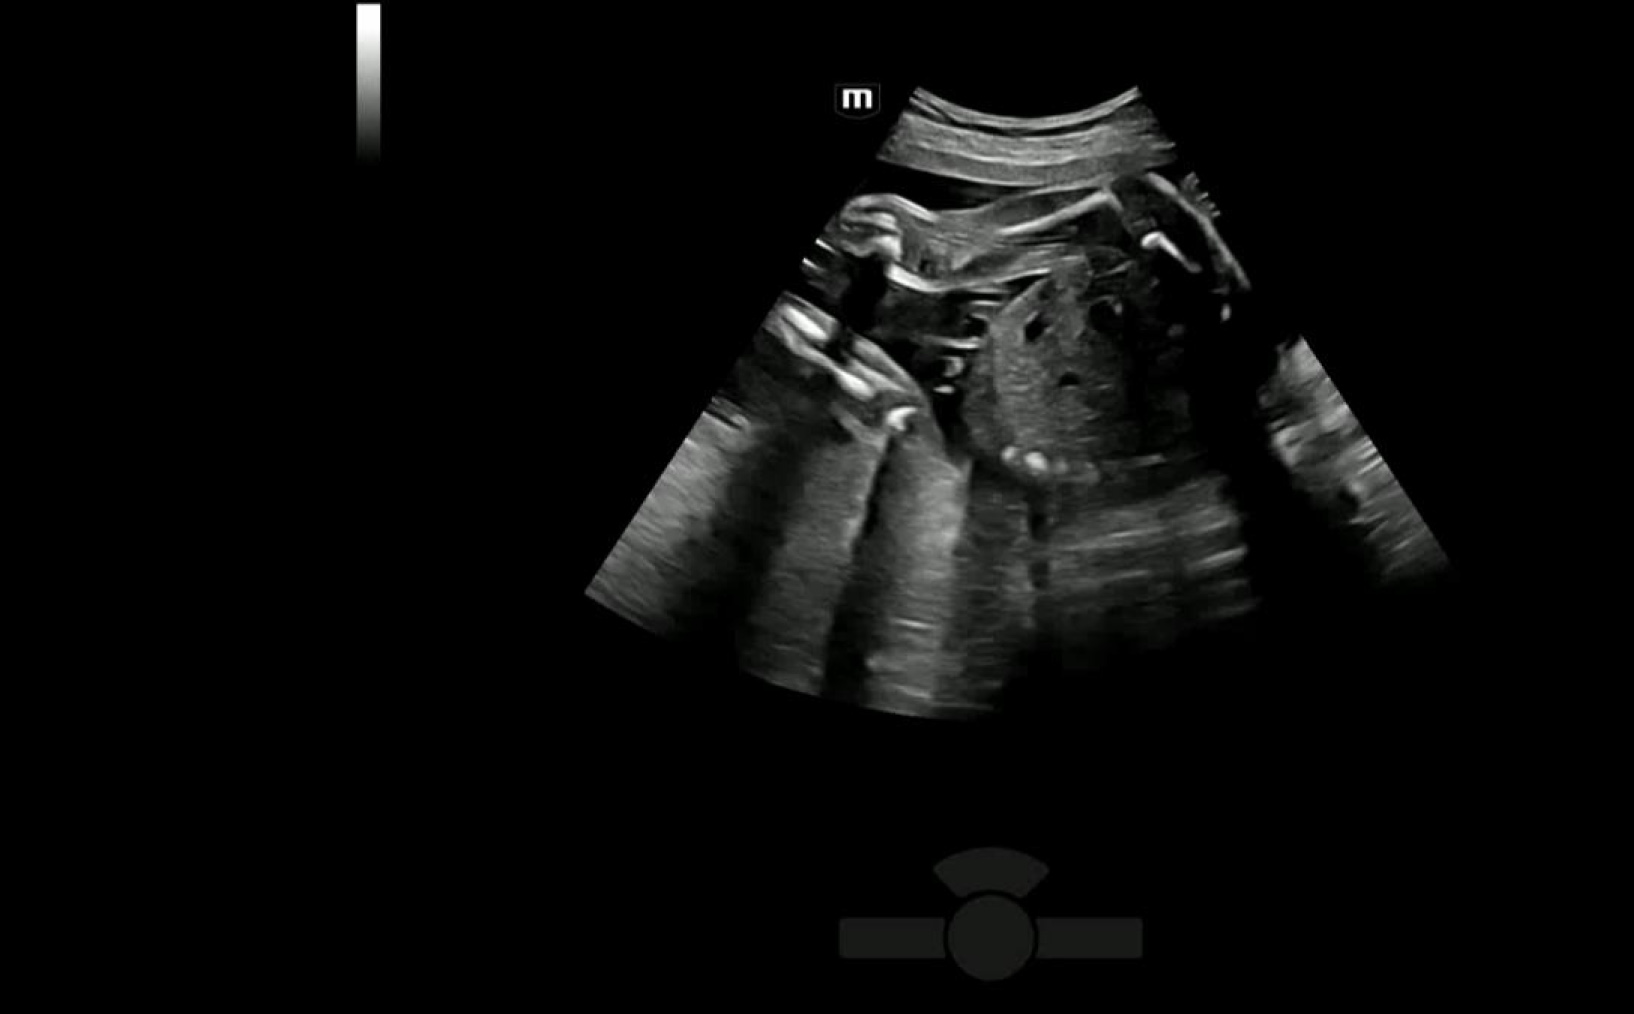

Легкое получение 3D изображения костей

- Автоматическое распознавание костей конечностей плода

- Автоматическая подстройка зоны интереса и положения до оптимального

- Автоматический рендеринг изображения